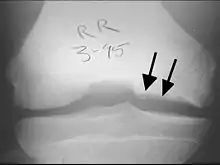

| A large flap lesion in the femur head typical of late stage Osteochondritis dissecans. In this case, the lesion was caused by avascular necrosis of the bone just under the cartilage. | |